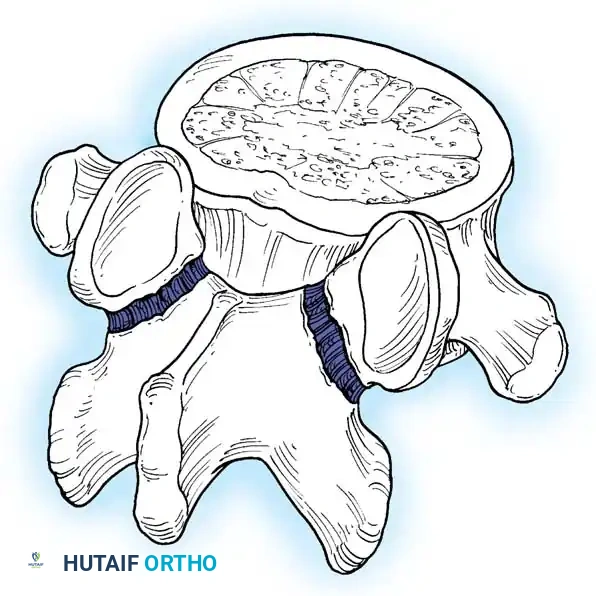

In adults, the degree of anterior translation (slip) is typically less than 50% (Grade I or II). This mechanical fault invariably leads to accelerated degeneration of the intervertebral disc at the level of the pars defect. The fundamental anatomical failure occurs at the pars interarticularis, which disrupts the integrity of the "bony hook" of the affected spinal motion segment.

The bony hook is a critical stabilizing structure consisting of the pedicle, the pars interarticularis, and the inferior articular facet of the cephalad segment, articulating with the superior articular facet of the caudal segment. When a spondylolytic defect occurs, this structural linkage is compromised and can no longer resist anterior translational shear forces. Consequently, the posterior elements separate through the pars fracture—leaving the facet joints anatomically located—while the entire trunk and anterior vertebral column translate anteriorly over the sacrum.